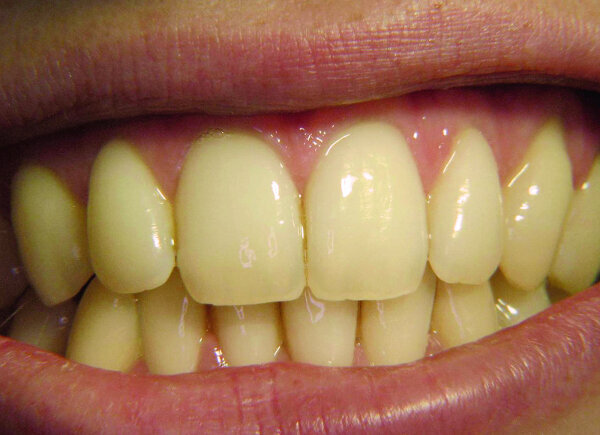

Si l’on considère les mâchoires sous cet angle insolite, le maxillaire solidement attaché au crâne est l’image de nos désirs (Fig. 1). En particulier, sa largeur et les dents alignées régulièrement dans l’arcade indiquent que le patient ou la patiente est capable d’exprimer ses souhaits, et la communication avec cette personne ne posera donc aucune difficulté (Fig. 2).

Par contre, un maxillaire étroit, où les incisives et les canines s’articulent en occlusion inversée antérieure, reflète une personne passive avec qui les échanges seront moins aisés. De telles difficultés à exprimer les désirs et les sentiments dans la vie sont signalées chez les porteurs d’une prothèse maxillaire complète, par exemple (Fig. 3).